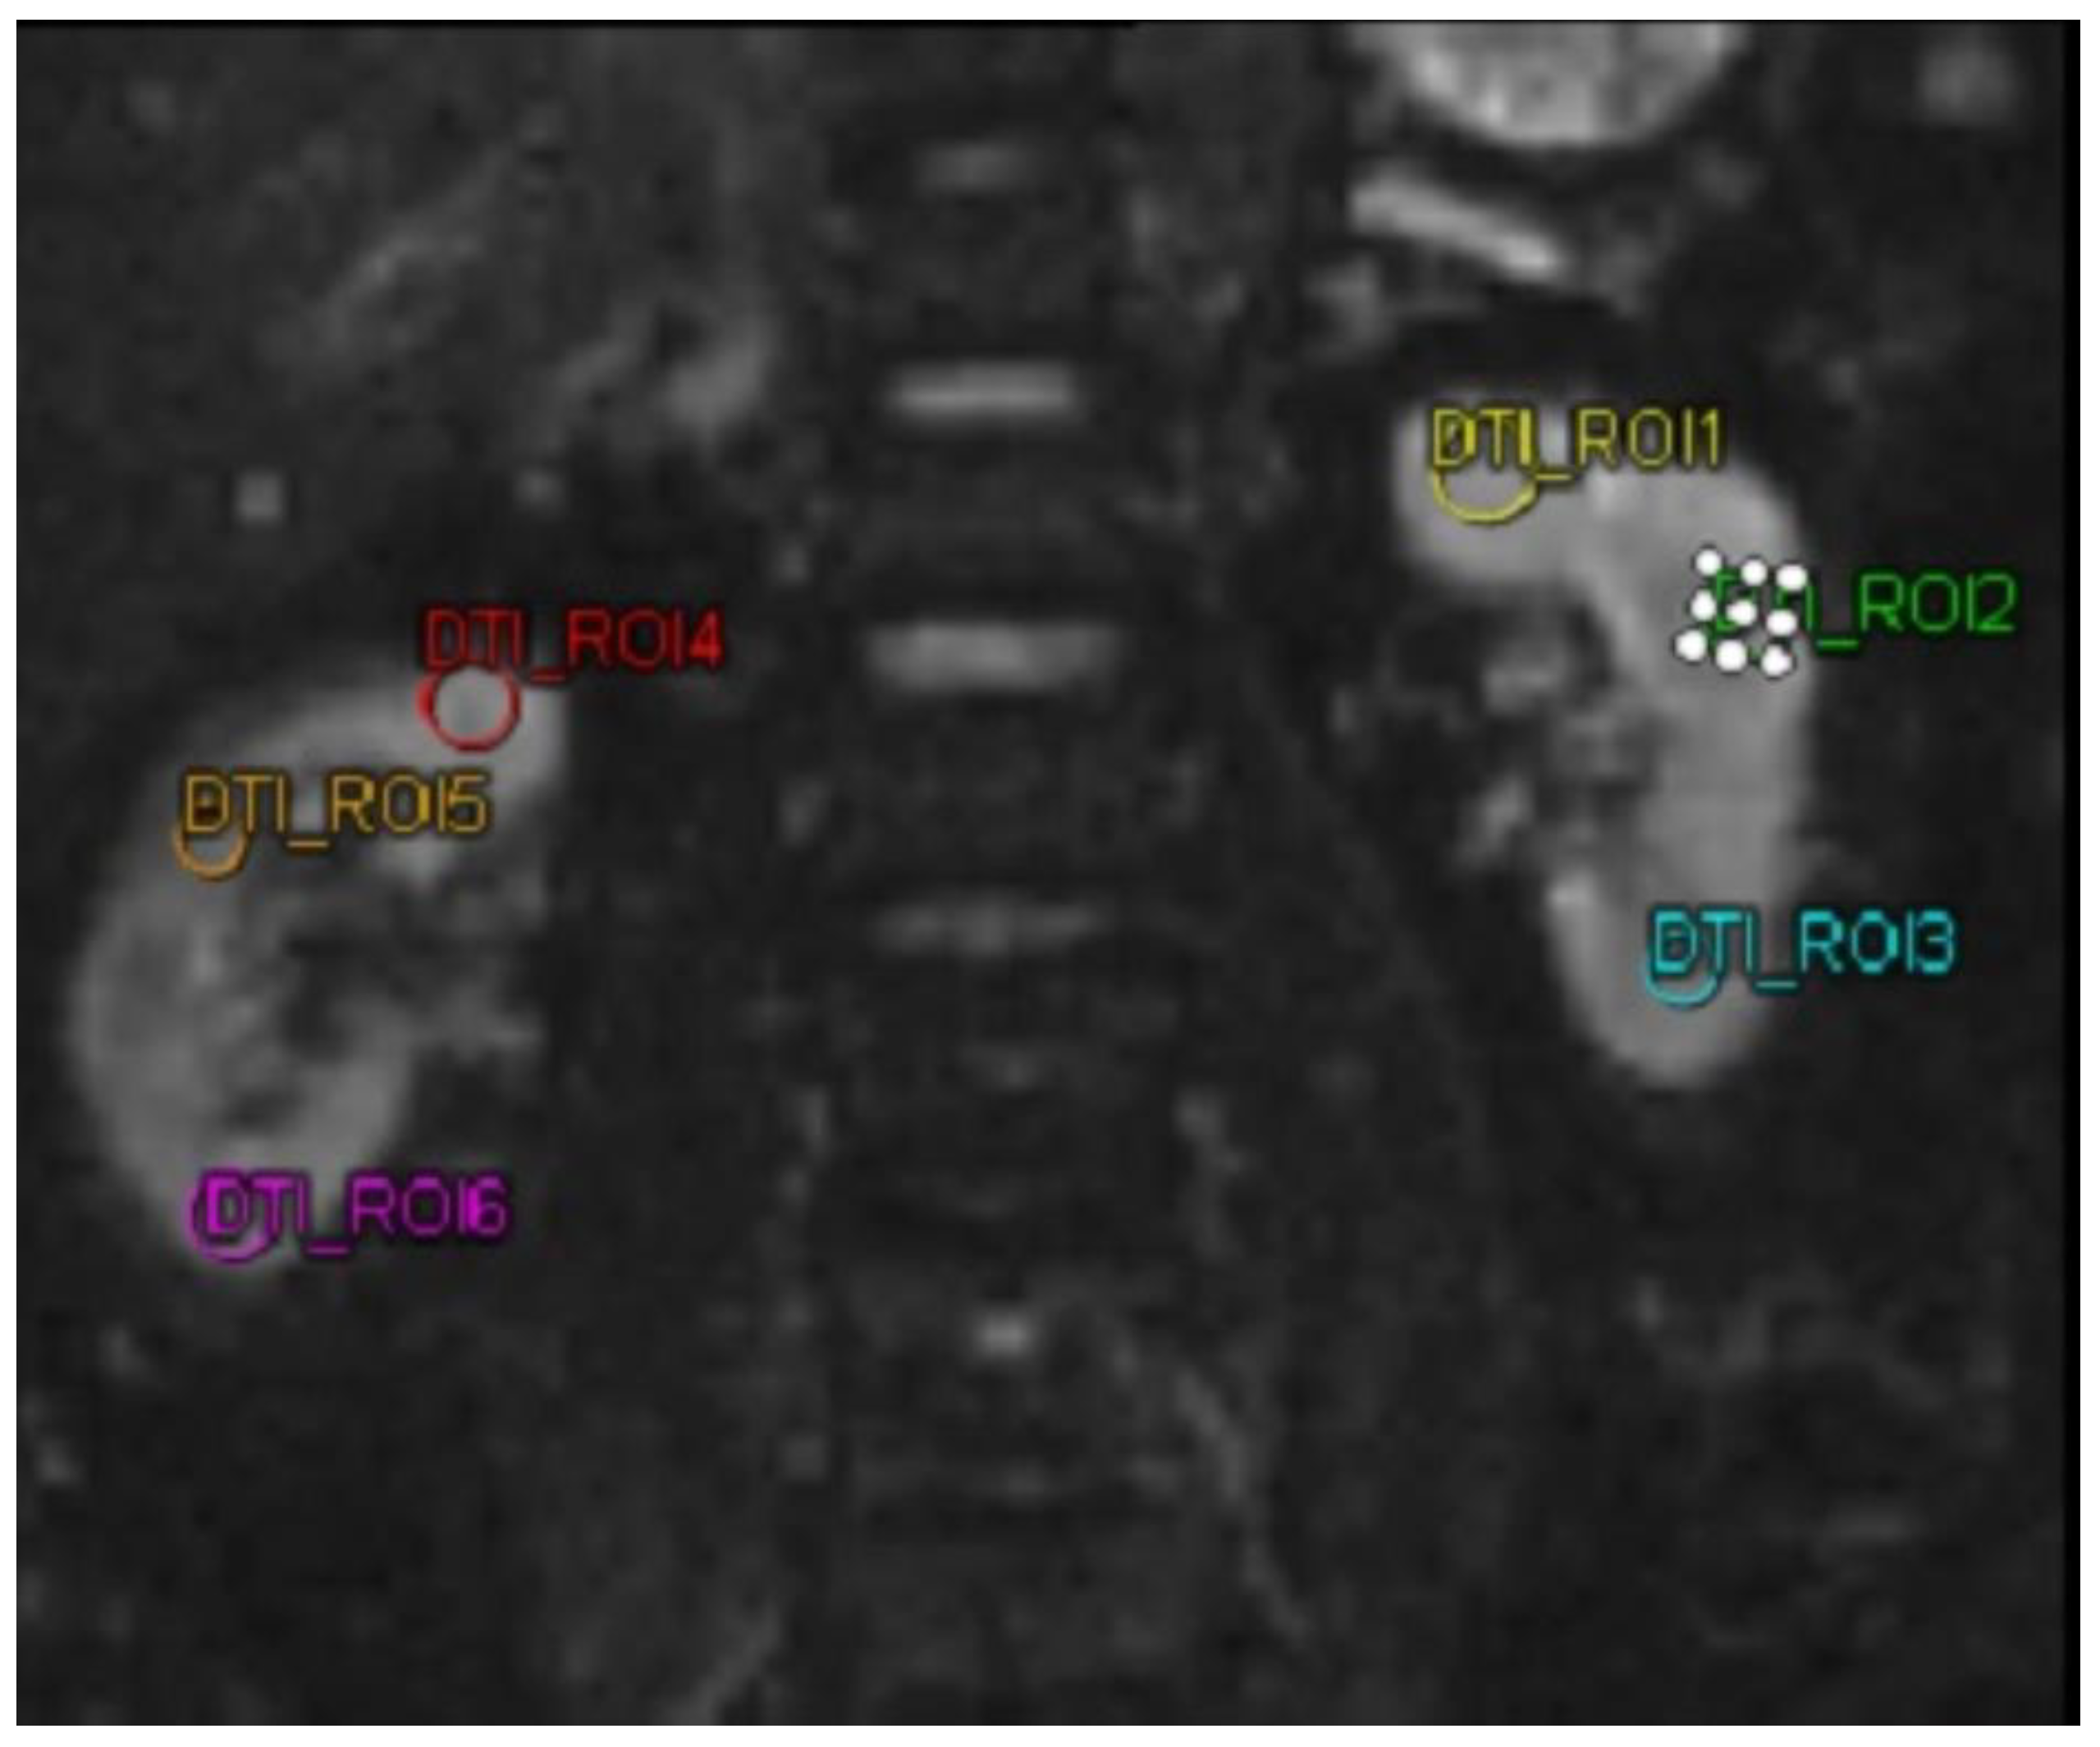

MMP-9 and ICAM-1 biomarkers were examined using a sandwich-ELISA kit (Reed Biotech Ltd). DTI MRI imaging examination in this study used a MAGNETRON Vida MRI scanner (Siemens,Erlangen,Germany). DTI MRI examination was performed on both kidneys of the subject. Then the subject was subjected to 3 ROIs in each kidney. After obtaining the FA value. In this study, FA was taken, with a decrease and increase in FA in patients.

Table 2 shows the analysis of FA, MMP-9, and ICAM-1. In DTI MRI measurements (FA) before and after administration of autologous dendritic cells (Figure 2), the median value before administration was 242.57 ± 63.97. After administration of autologous dendritic cells, the median value increased to 305.61 ± 152.32. Statistical tests showed a significant difference with a p-value = 0.042. Figure 3a shows box and whisker FA on DTI MRI.

Figure 2. MRI DTI examination on a patient using 6 different region of interests. Abbreviations: MRI-DTI : Magnetic Resonance Imaging - Diffusion Tensor Imaging.